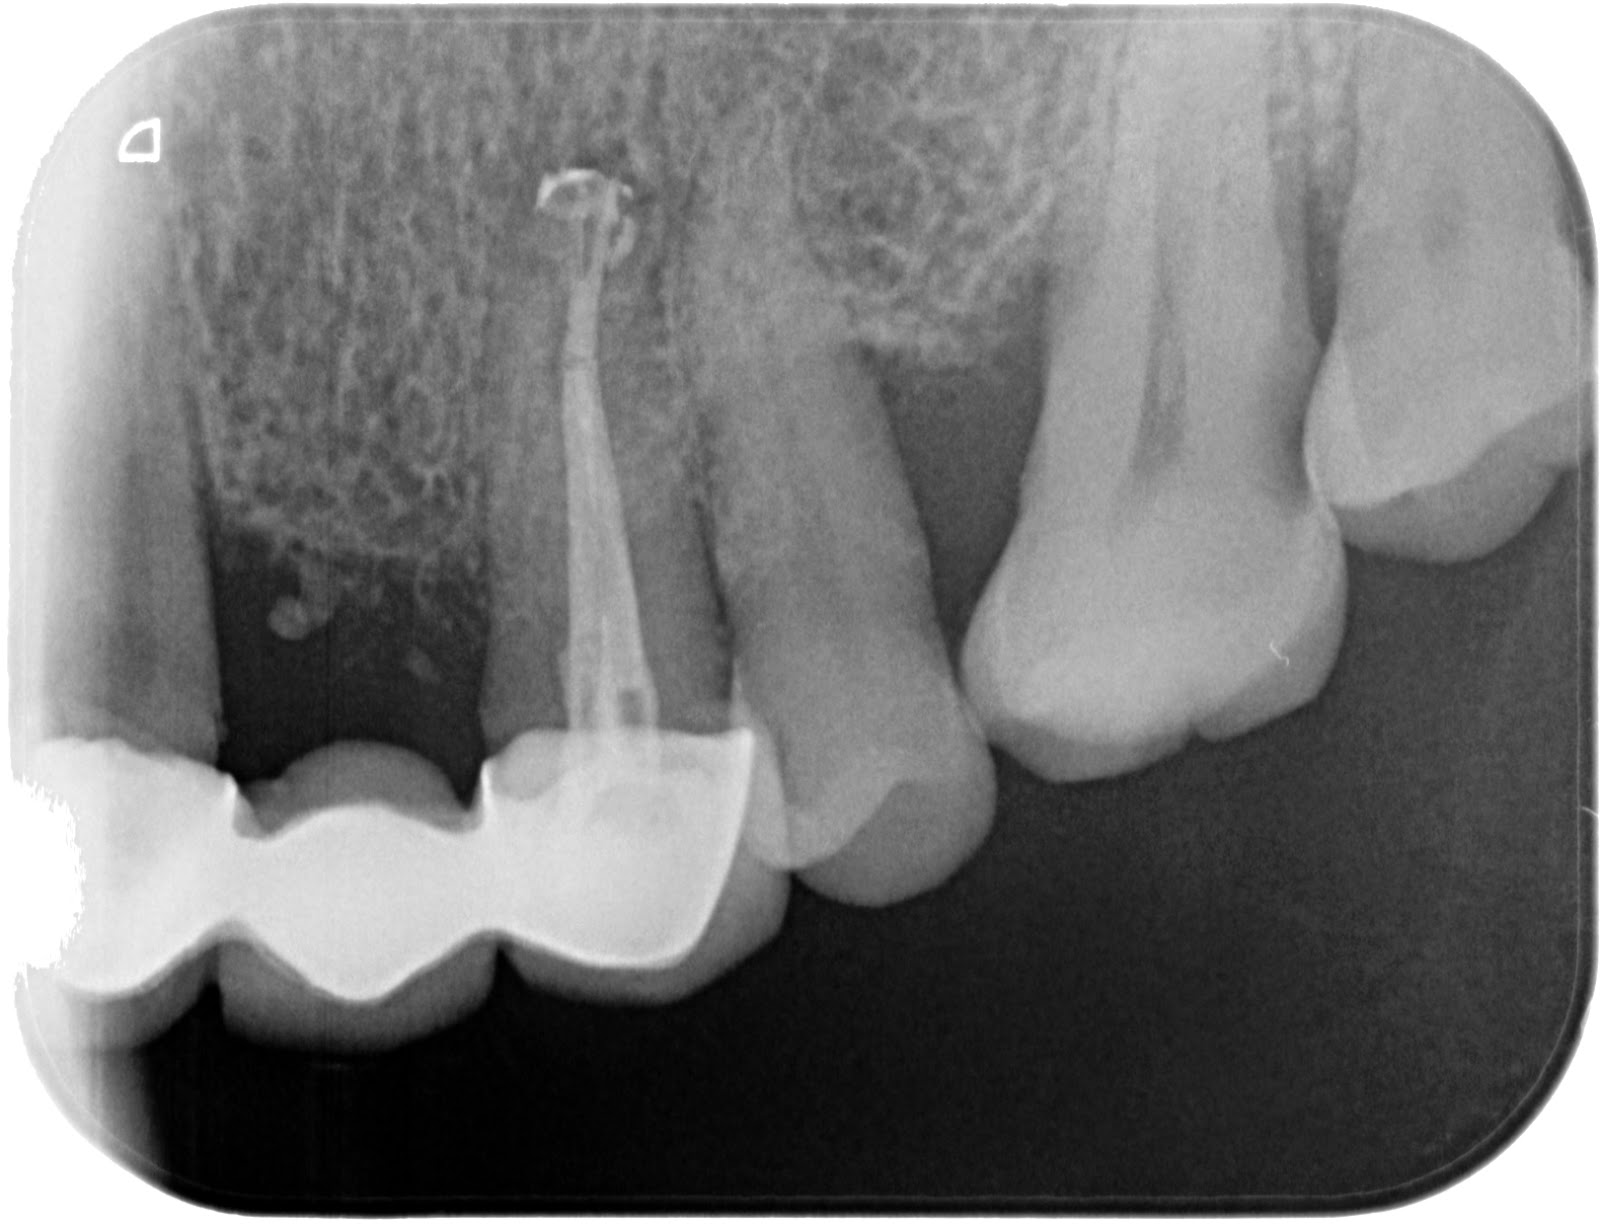

- Realizamos Rx de conductometría y nuestra primera impresión es

que se trata de una raíz con configuración 2:1 ( tipo II de Vertucci).

- A la hora de obturar, realizamos una conometría con cemento Top

seal, y observamos con sorpresa que puede que exista otra salida, lo que

correspondería con el  conducto Palatino.

Pudiendo tratarse de una configuración 2-1-2 (Tipo VI de Vertucci)

- En la radiografía de condensación observamos como se nos ha

rellenado el conducto de Vestibular de gutapercha y a su vez el otro conducto

(¿palatino?).

Nos queda la duda de si en realidad se trataba realmente de un

conducto palatino (Raíz tipo VI de Vertucci) o un conducto lateral con el

mismo aspecto.

¿Qué opináis vosotros?